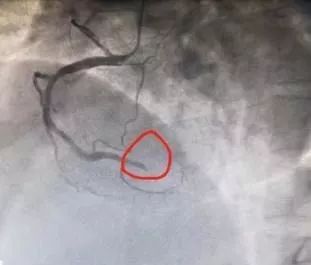

术前

患者由心血管科迅速转运至介入诊疗室,田军主任医师和徐林东副主任医师在局麻下,经右侧桡动脉穿刺行冠脉造影检查发现:患者右冠状动脉远段完全闭塞,血流完全中断,必须行PCI治疗开通闭塞血管。迅速将病情告知家属并再次征得同意后,紧急行右冠状动脉远段球囊扩张术及支架置入术。在为患者成功置入一枚支架后,造影显示支架膨胀良好,血管狭窄消失,血流恢复正常,患者胸痛症状完全消失,转危为安。